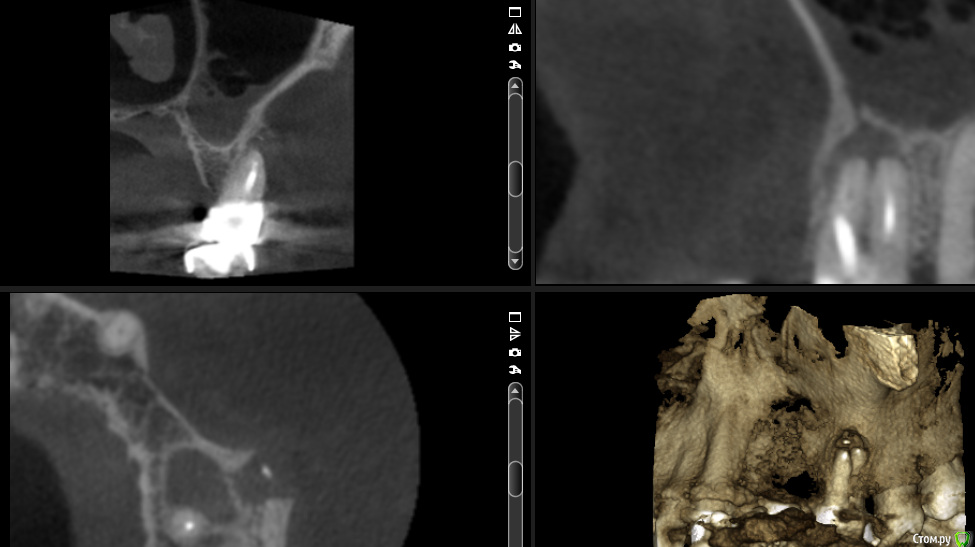

Карен Аванесов Опубликовано 29 августа, 2016 Поделиться Опубликовано 29 августа, 2016 (изменено) Если Ваше решение будет зависеть от количества "за" и "против", я за удаление и возможно по результатам КТ, пазуху санировать придется перед синуслифтингом. Изменено 29 августа, 2016 пользователем Карен Аванесов 2 Ссылка на комментарий

___49___ Опубликовано 29 августа, 2016 Автор Поделиться Опубликовано 29 августа, 2016 Мне необходимо мнение ваше - коллег ....оно совпадает с моим)) , До КТ надеялся, что изменения только у апексов щечных корней верхней трети, без вовлечения пазухи и небного корня....но не тут то было . . Ссылка на комментарий